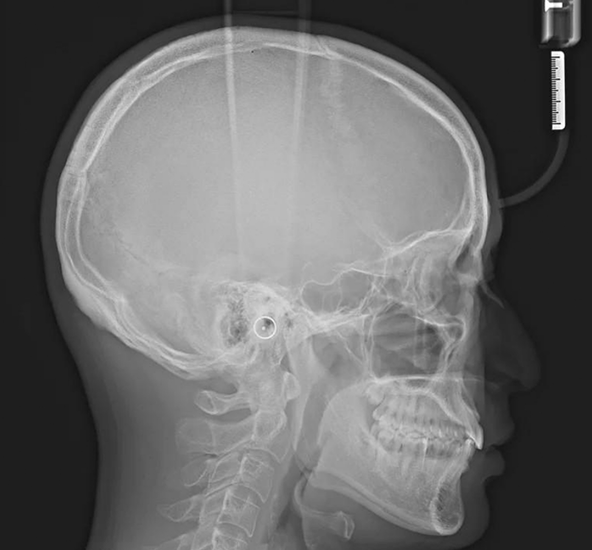

当院では、最新型のiTero Luminaによる高精度な口腔内スキャニングと、セファログラム(頭部X線規格写真)などの検査データを組み合わせて診断を行っています。

歯並びだけでなく、骨格バランスや横顔のラインまで多角的に分析することで、従来の検査よりも精密で総合的な治療計画の立案を可能にしています。

矯正治療に必要なセファログラムを併用することで、頭部全体の骨格バランスや将来的な変化まで考慮した分析が可能になります。

その結果、より精度の高い治療計画を立てることができ、仕上がりの安定性にもつながります。